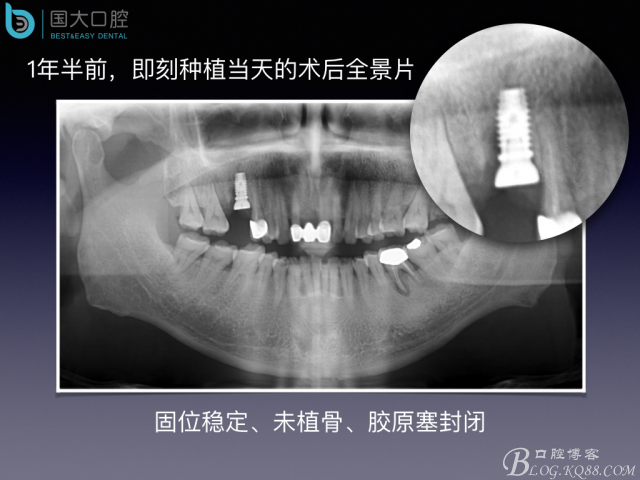

嚴(yán)重根尖周炎能做即刻種植嗎?